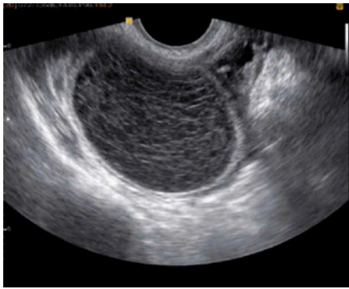

Paciente de 24 anos, comparece ao pronto socorro

com queixa de dor em região suprapúbica e na fossa

ilíaca à direita, com início há cerca de 2 dias e piora

progressiva. Nega queixas urinárias ou

gastrointestinais. Menarca aos 12 anos, sexarca aos

18 anos, vida sexual ativa com parceiro único, com

uso de preservativo masculino. Método

contraceptivo: DIU de cobre. A data da última

menstruação foi há 2 semanas e 5 dias. Ao exame

físico, bom estado geral, estável

hemodinamicamente, mucosas coradas; dor à

palpação profunda da fossa ilíaca direita, sem sinais

de peritonite. Ao toque vaginal, identifica-se massa

palpável na mesma topografia.

A USG-TV veio com o seguinte achado:

Frente a essas informações, qual a melhor hipótese diagnóstica?